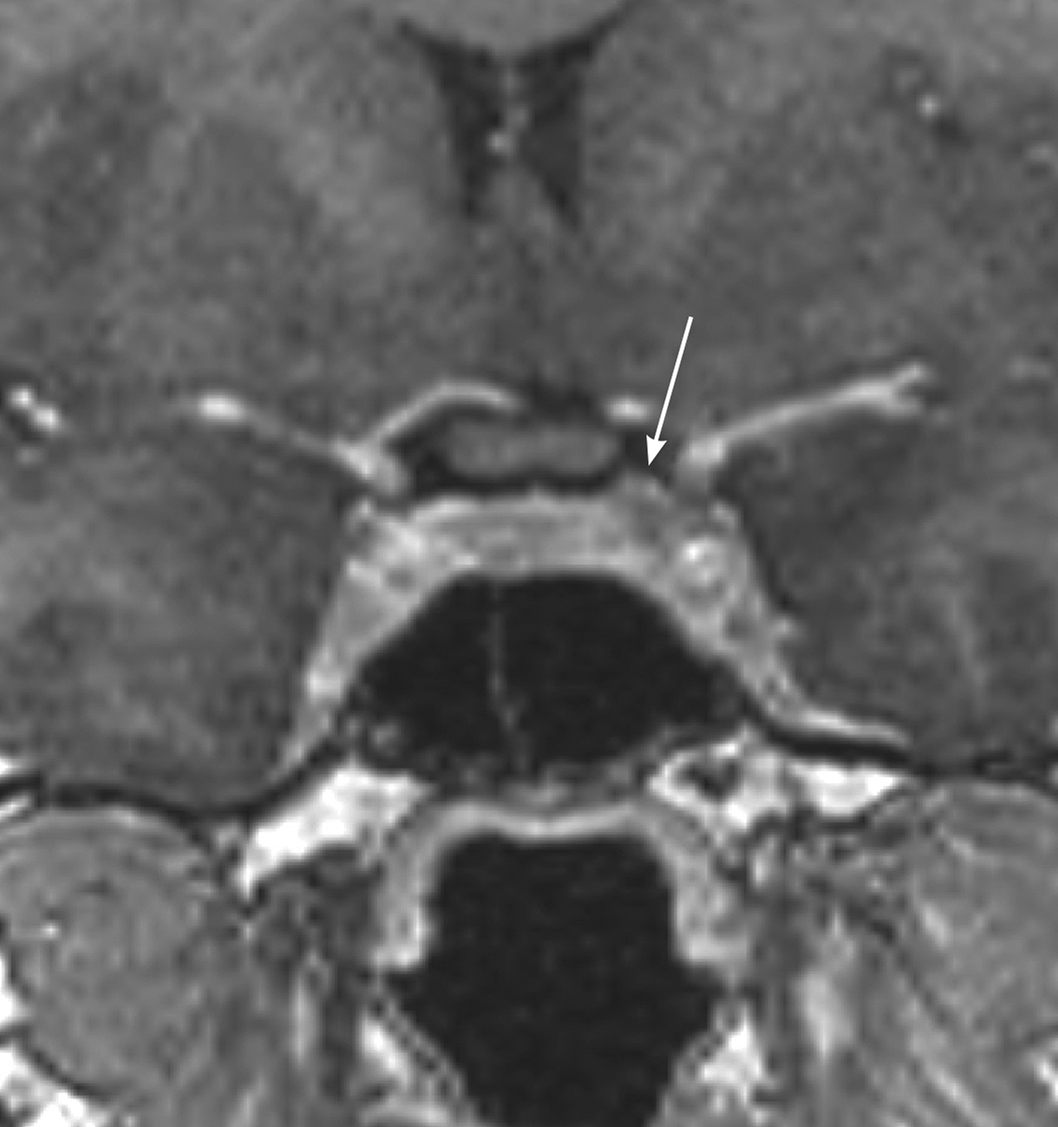

MRI scan of a microprolactinoma

Figure. MRI with arrow showing left-sided microprolactinoma, which was removed at trans-sphenoidal surgery with positive histology and subsequent remission. ©Mark Gurnell, Addenbrooke’s Hospital